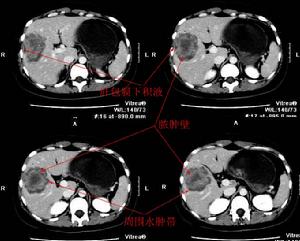

1.CT檢查CT片中顯示液體的積聚,特別是積聚液體中存在氣體是膿腫形成的病理特徵,膿腫中存在氣體是主要的標誌。